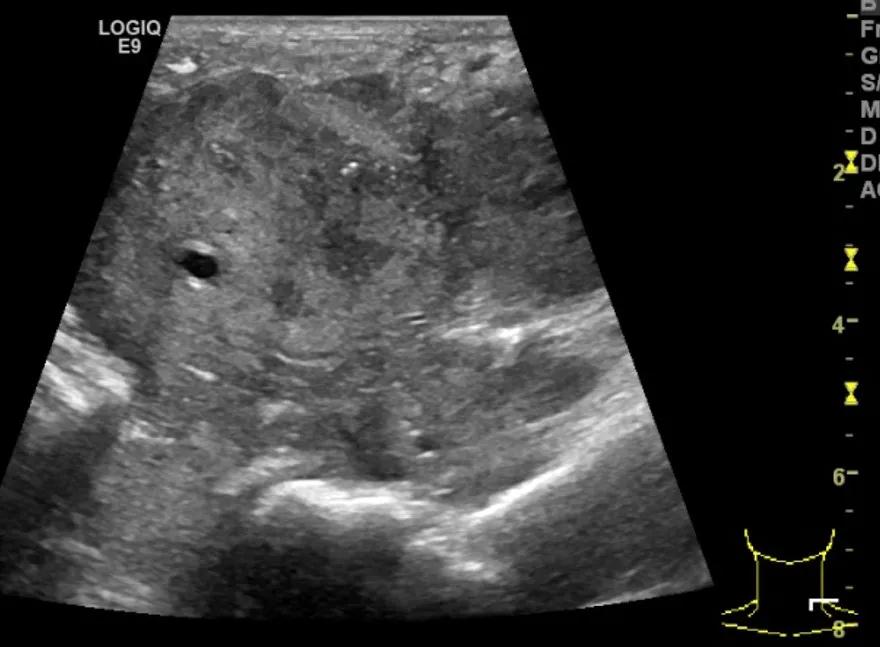

第三例是甲状腺癌患者,双侧甲状腺癌切除术后、碘治疗后一年余效果欠佳,超声显示左颈3区3枚低回声结节,穿刺示甲状腺乳头状癌转移。患者不愿意手术,希望采取局部治疗。对病灶进行液体隔离后采取热消融术,由于淋巴结较小,热消融一分钟左右完全灭活,术后增强影像显示没有脏器充填。

(病例3图例)